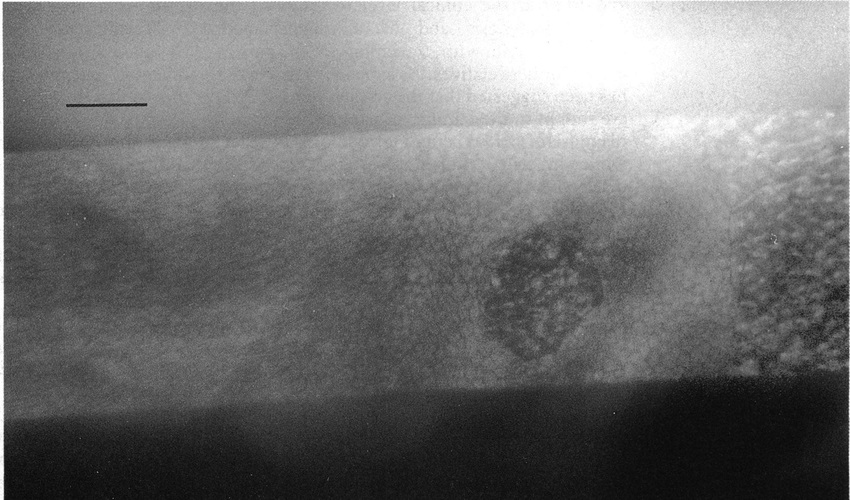

이경우에도 각막부종이 발생한 그부위를 확대해서 관찰하면

ICE syndrome 에서 나타나는 특징적인 ICE cell 의 모습을 관찰할수 있습니다.